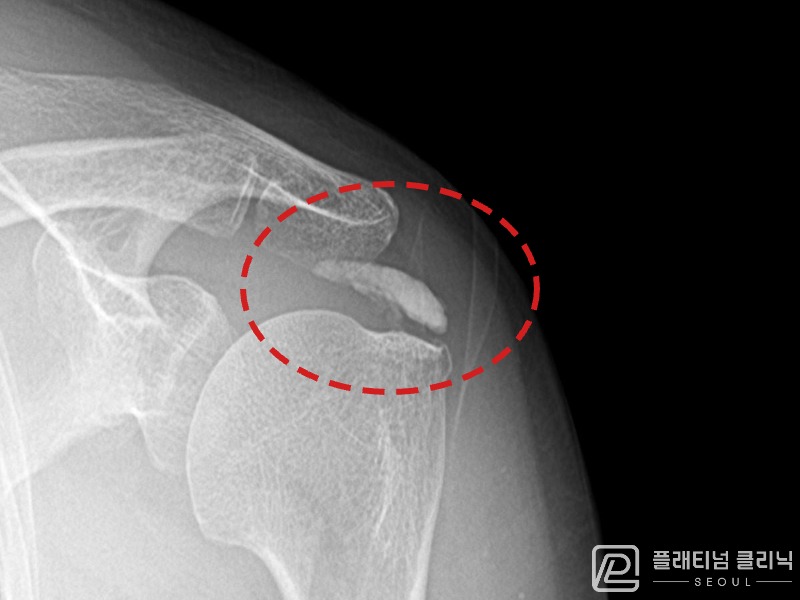

[촬영시기:21.10.21~21.10.30]

[석회분쇄흡입술] 우측 어깨 통증과 운동 제한으로 일상생활이 불편해진 30대 여성 환자로, X-ray에서 우측 극상근건 내 석회 침착이 확인되어 석회분쇄흡입술을 시행하였습니다.